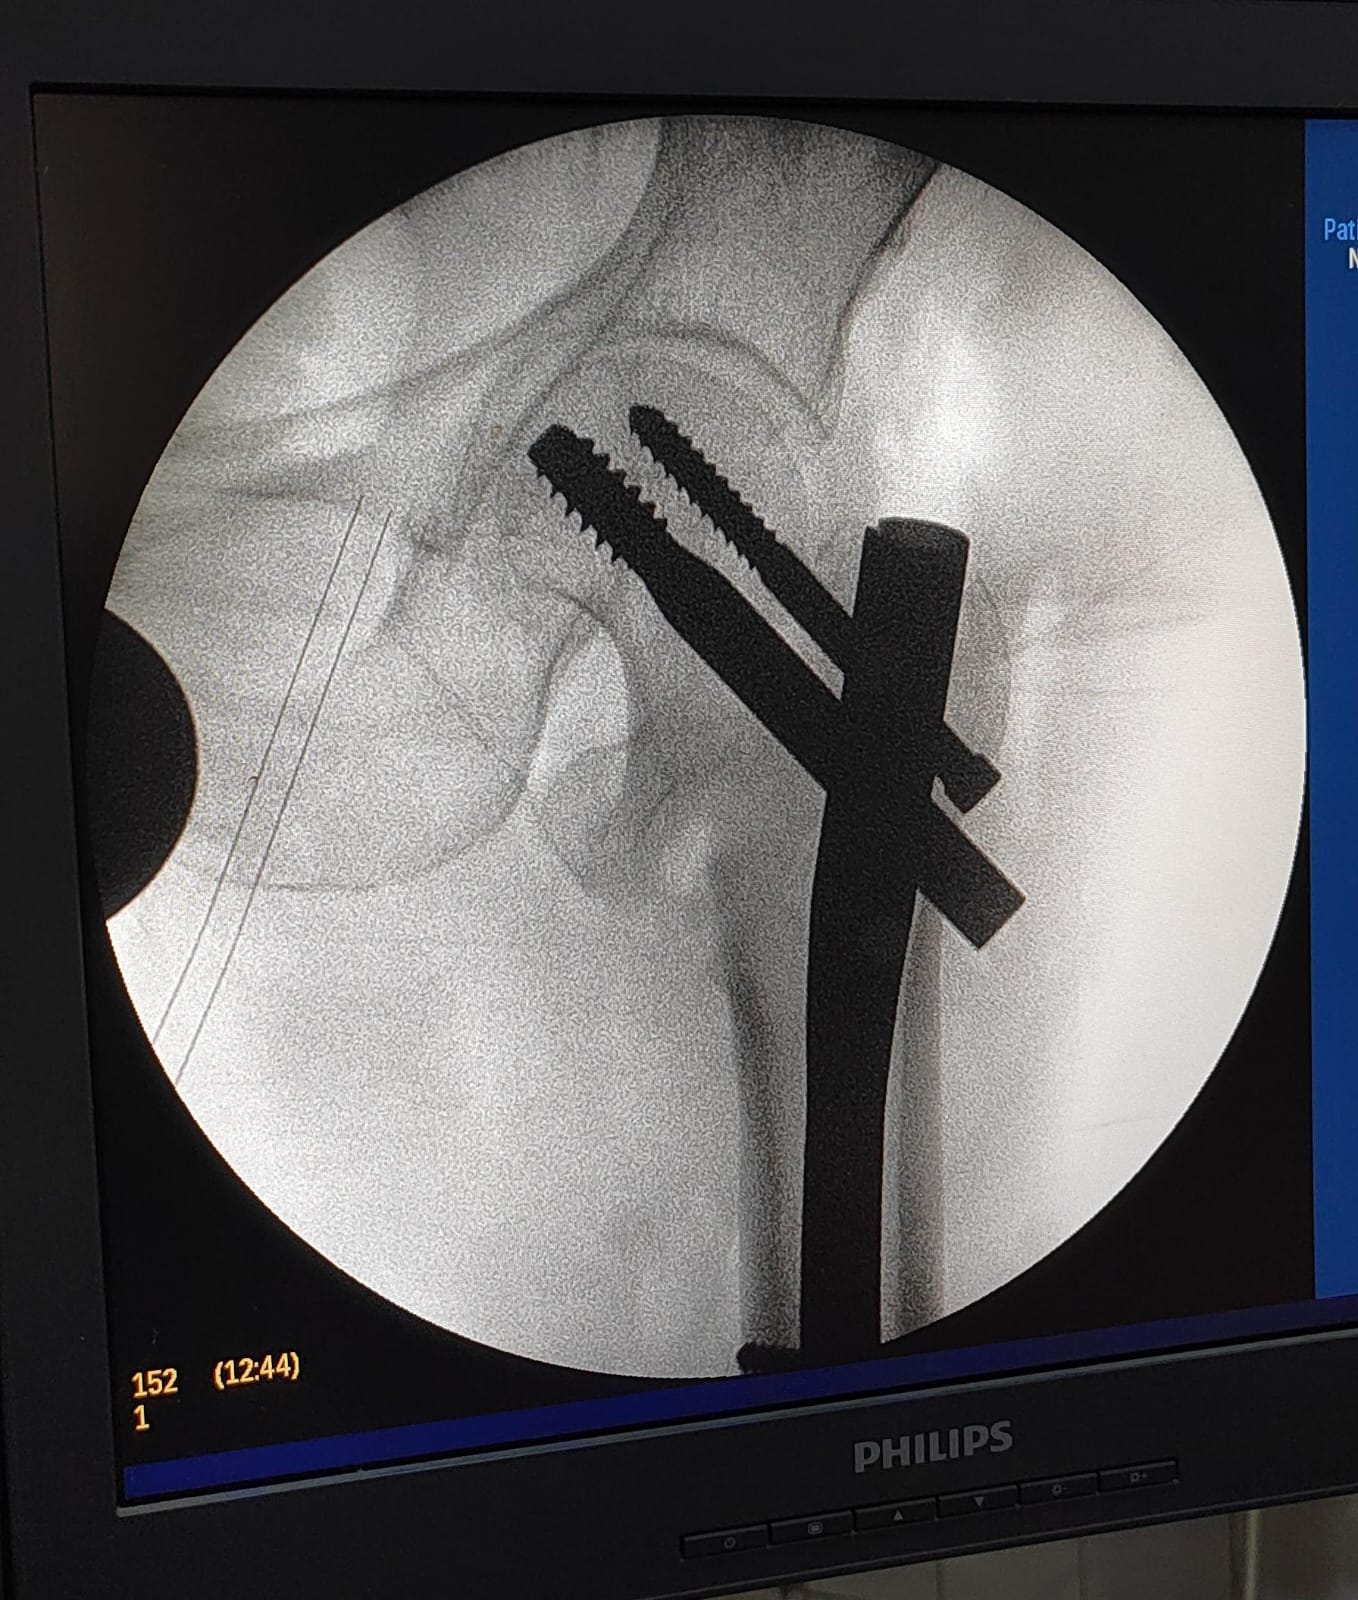

تركيب كويرات بالرضفة اليسرى لمريض.

تركيب مسمار نخاعي بالفخذ الأيسر لمريض آخر.

وقد تمت العمليتان بدقة عالية وباستخدام أحدث التقنيات، وشارك فيهما فريق طبي وتمريضي وفني متكامل ضم:

الأطباء: د. شريف البيومي توفيق (عظام)، د. عيد السيد حسن (عظام)، د. ماهر فوزي كامل (تخدير).